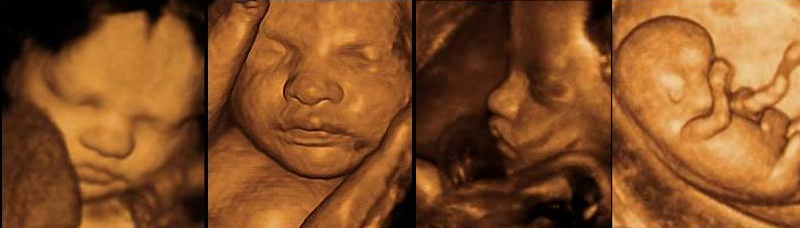

Resim Açıklama